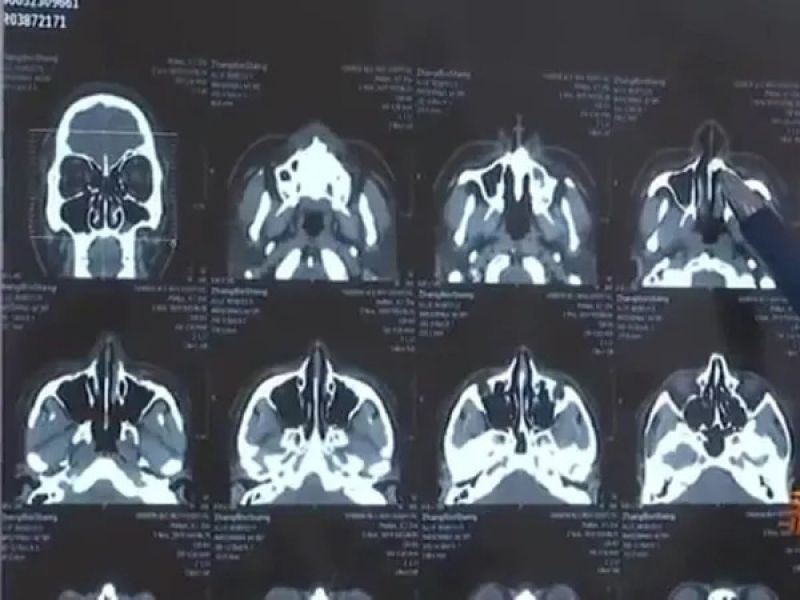

ਚੀਨ ਦੇ ਝਾਂਗ ਬਿੰਸੇਂਗ (Zhang Binsheng) ਨੂੰ 3 ਮਹੀਨੇ ਤੋਂ ਆਪਣੇ ਨੱਕ ਜ਼ਰੀਏ ਸਾਹ ਲੈਣ ਵਿਚ ਸਮੱਸਿਆ ਹੋ ਰਹੀ ਸੀ। ਫਿਰ ਉਸ ਨੇ ਡਾਕਟਰਾਂ ਨੂੰ ਦਿਖਾਉਣ ਦਾ ਫੈਸਲਾ ਲਿਆ। ਝਾਂਗ ਨੇ ਡਾਕਟਰਾਂ ਨੂੰ ਦੱਸਿਆ ਕਿ ਉਹ ਰਾਤ ਵੇਲੇ ਸੌਂ ਨਹੀਂ ਪਾਉਂਦਾ ਅਤੇ ਉਸ ਨੂੰ ਸਾਹ ਲੈਣ ਵਿਚ ਮੁਸ਼ਕਲ ਹੁੰਦੀ ਹੈ। ਉਨ੍ਹਾਂ ਨੇ ਆਪਣੀ ਨੱਕ ਵਿਚੋਂ ਲਗਾਤਾਰ ਗੰਧ ਆਉਣ ਦੀ ਵੀ ਸ਼ਿਕਾਇਤ ਕੀਤੀ। ਡਾਕਟਰਾਂ ਨੇ ਉਸ ਨੂੰ ਐਕਸ ਰੇਅ ਕਰਾਉਣ ਦੀ ਸਲਾਹ ਦਿੱਤੀ।

ਜਦੋਂ ਐਕਸ ਰੇਅ ਦੀ ਰਿਪੋਰਟ ਆਈ ਤਾਂ ਝਾਂਗ ਆਪਣੀ ਨੱਕ ਦੀ ਨਲੀ ਦੇ ਪਿੱਛੇ ਉੱਚ ਘਣਤਾ ਵਾਲਾ ਪਰਛਾਵਾਂ ਦੇਖ ਕੇ ਹੈਰਾਨ ਰਹਿ ਗਿਆ। ਡਾਕਟਰਾਂ ਦਾ ਮੰਨਣਾ ਸੀ ਕਿ ਇਹ ਪਰਛਾਵਾਂ ਝਾਂਗ ਦੀ ਨੱਕ ਵਿਚ ਉੱਗ ਆਏ ਦੰਦ ਦਾ ਸੀ, ਜੋ ਇਕ ਹਾਦਸੇ ਦੇ ਕਾਰਨ ਉਸ ਦੀ ਨੱਕ ਵਿਚ ਉੱਗ ਆਇਆ ਸੀ। ਰਿਪੋਰਟ ਮੁਤਾਬਕ ਜਦੋਂ ਝਾਂਗ 10 ਸਾਲ ਦਾ ਸੀ ਉਦੋਂ ਉਹ ਇਕ ਮਾਲ ਦੀ ਤੀਜੀ ਮੰਜ਼ਿਲ ਤੋਂ ਹੇਠਾਂ ਡਿੱਗ ਪਿਆ ਸੀ। ਉਸ ਦੇ ਦੋ ਦੰਦ ਟੁੱਟੇ ਸਨ ਪਰ ਹਾਦਸੇ ਦੇ ਬਾਅਦ ਸਿਰਫ ਇਕ ਟੁੱਟੇ ਹੋਏ ਦੰਦ ਨੂੰ ਲੱਭਿਆ ਜਾ ਸਕਿਆ ਸੀ।

ਡਾਕਟਰਾਂ ਦੇ ਮੁਤਾਬਕ ਅਜਿਹਾ ਲੱਗਦਾ ਹੈ ਕਿ ਦੂਜਾ ਦੰਦ ਕਿਸੇ ਤਰ੍ਹਾਂ ਜੜ ਤੋਂ ਉਖੜ ਗਿਆ ਅਤੇ ਉਸ ਦੇ ਨੱਕ ਦੇ ਅੰਦਰ ਉੱਗ ਗਿਆ। ਇਸ ਗੱਲ 'ਤੇ ਦੋ ਦਹਾਕਿਆਂ ਤੱਕ ਨਾਂ ਤਾਂ ਝਾਂਗ ਨੇ ਅਤੇ ਨਾ ਹੀ ਉਸ ਦੇ ਪਰਿਵਾਰ ਨੇ ਧਿਆਨ ਦਿੱਤਾ। ਅੱਜ ਝਾਂਗ ਦੀ ਉਮਰ 30 ਸਾਲ ਹੋ ਚੁੱਕੀ ਹੈ।ਭਾਵੇਂਕਿ 30 ਮਿੰਟ ਦੀ ਸਰਜਰੀ ਦੇ ਬਾਅਦ ਝਾਂਗ ਦੀ ਨੱਕ ਤੋਂ ਇਕ ਸੈਂਟੀਮੀਟਰ ਲੰਬੇ ਦੰਦ ਨੂੰ ਕੱਢਿਆ ਗਿਆ, ਜਿਸ ਮਗਰੋਂ ਉਸ ਨੇ ਸੁੱਖ ਦਾ ਸਾਹ ਲਿਆ।